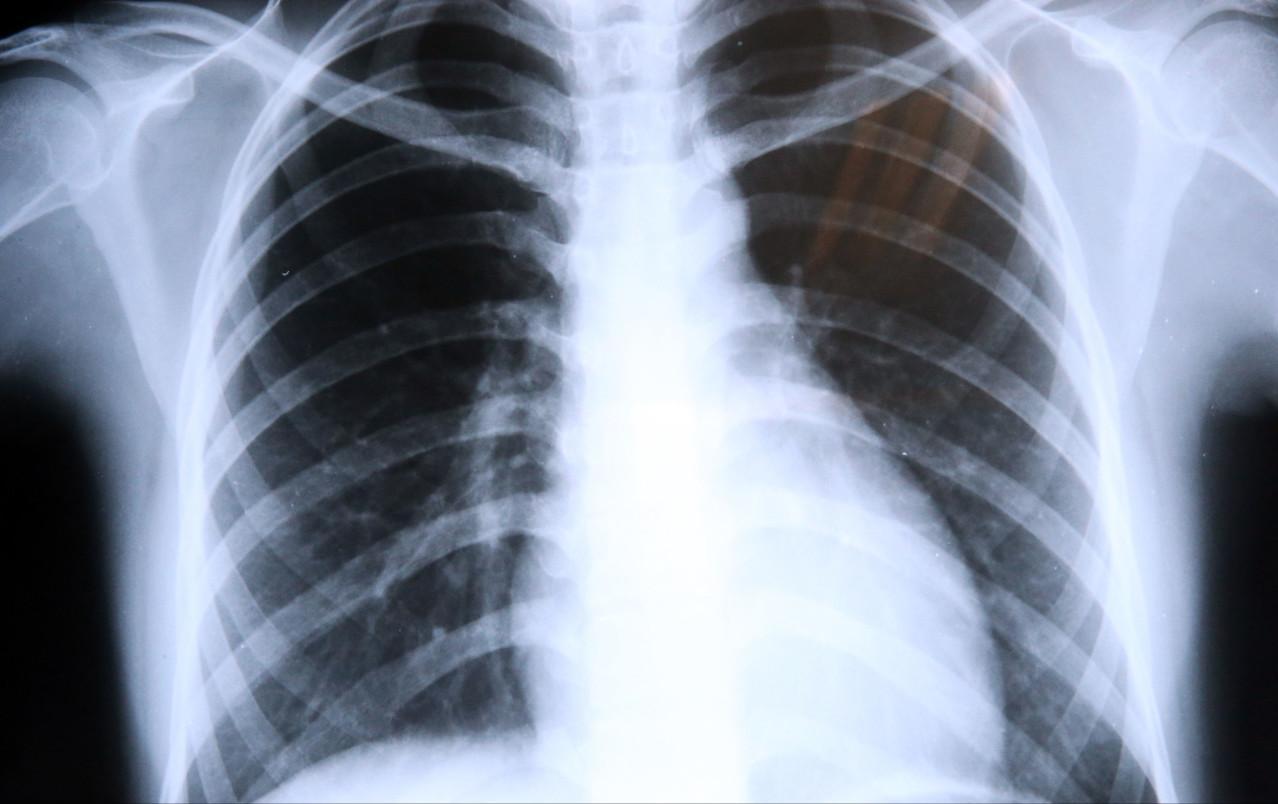

警惕无症状晚期肺癌,两肺到处是肿瘤患者却毫无感觉,诊断即晚期

肺是一个不敏感的器

不知不觉就得了晚期肺癌,有人甚至觉得自己很健康,其实早有预兆

毫无症状的晚期肺癌

无症状肺癌是如何形成的,很多人完全没有意识到症状,发现时已迟

门诊上经常碰到没有

警惕“无症状”晚期肺癌,有些人转移了还没有意识到,发现已晚

肺癌是毫无争议的癌王